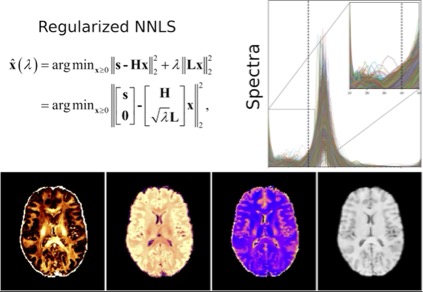

4. Myelin Water Imaging Using T2 Relaxometry

Myelin is a lipid-rich substance that surrounds the axons in the brain, which is essential for the proper functioning of the nervous system. Myelin water imaging is a magnetic resonance imaging (MRI) method that can be used to quantify and visualize myelination in the brain and spinal cord in vivo. The signal coming from the MRI machine (using a multi-echo T2 relaxometry sequence) can be decomposed into components, including that originated by water molecules trapped between the lipid bilayers of myelin. The correct estimation of this component provides a myelin-specific MRI biomarker to monitor brain changes in cerebral white matter. Myelin quantification has important implications for understanding various neurodegenerative diseases, including multiple sclerosis.

We are looking for a motivated student to (1) learn about the MRI and signal processing theory behind this modality, (2) improve the current estimation methods, and (3) test and compare the new results with the current methods and histological measurements.

The project builds on top of previous cutting-edge research carried out in our lab (for more details see our multi-component T2 reconstruction toolbox and related references: https://github.com/ejcanalesr/multicomponent-T2-toolbox). The results will be published in international conferences and relevant journals.

4. Myelin Water Imaging Using T2 Relaxometry

Myelin is a lipid-rich substance that surrounds the axons in the brain, which is essential for the proper functioning of the nervous system. Myelin water imaging is a magnetic resonance imaging (MRI) method that can be used to quantify and visualize myelination in the brain and spinal cord in vivo. The signal coming from the MRI machine (using a multi-echo T2 relaxometry sequence) can be decomposed into components, including that originated by water molecules trapped between the lipid bilayers of myelin. The correct estimation of this component provides a myelin-specific MRI biomarker to monitor brain changes in cerebral white matter. Myelin quantification has important implications for understanding various neurodegenerative diseases, including multiple sclerosis.

We are looking for a motivated student to (1) learn about the MRI and signal processing theory behind this modality, (2) improve the current estimation methods, and (3) test and compare the new results with the current methods and histological measurements.

The project builds on top of previous cutting-edge research carried out in our lab (for more details see our multi-component T2 reconstruction toolbox and related references: https://github.com/ejcanalesr/multicomponent-T2-toolbox). The results will be published in international conferences and relevant journals.